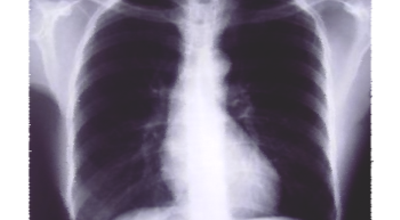

일반인이 근육의 통증과 금이 간 경우의 차이는 거의 판별하기 힘들게 됩니다. 갈비뼈라고 하는 부분이 눈에 보이도록 붓는 것도 아니고, 멍이 들어서 아픈것도 아니기 때문이예요. 가장 정확하게 판별하는 방법은 엑스레이를 찍는 방법이예요.